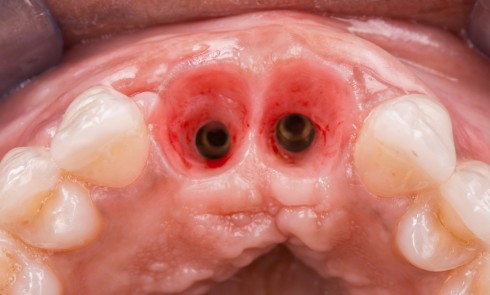

En mars 2016, la patiente se plaint d’une sensibilité sur la 25 et on note cliniquement une inflammation gingivale associée à un décalage apical du rebord marginal et de la ligne muco-gingivale en comparaison de leur situation visualisée au niveau des coiffes supra-implantaires. La couronne clinique est réduite et une infraposition avec une inocclusion d’environ 2 mm par rapport au plan d’occlusion et aux dents antagonistes est également notée (fig. 2 à 4). Un saignement au sondage ainsi qu’une poche de 5 mm en distal sont constatés. Le test de percussion est positif. Les tissus péri-implantaires adjacents ne présentent aucun signe de mucosite.

La radiographie péri-apicale au long cône confirme, sur la 25, un élargissement desmodontal, notamment en distal, des niveaux osseux mésio-distaux réduits par rapport aux clichés de contrôle précédents (les radiographies sont réalisées avec une technique parallèle avec des angulateurs de Rinn non personnalisés), un apex radiculaire normal et des niveaux osseux stables sur les implants adjacents (fig. 5). Le cisaillement systématique du fil dentaire lors de son passage confirme des points de contact très étroits entre 24, 25 et 26.